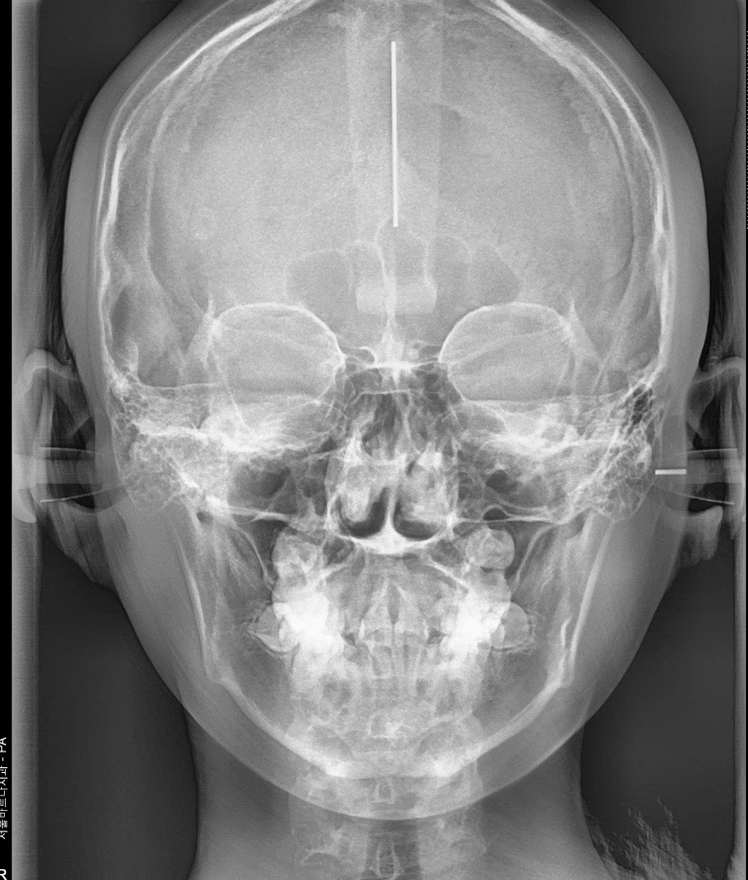

2단계: 정밀 검사 (X-ray 촬영 및 구외 사진)

얼굴 옆 모습을 찍는 x-ray도 찍고

정확한 검사를 위해 머리띠를 쓰고 찍을 때가 있는데

환자분들이 싫어하시더라고요ㅠㅠ

241116